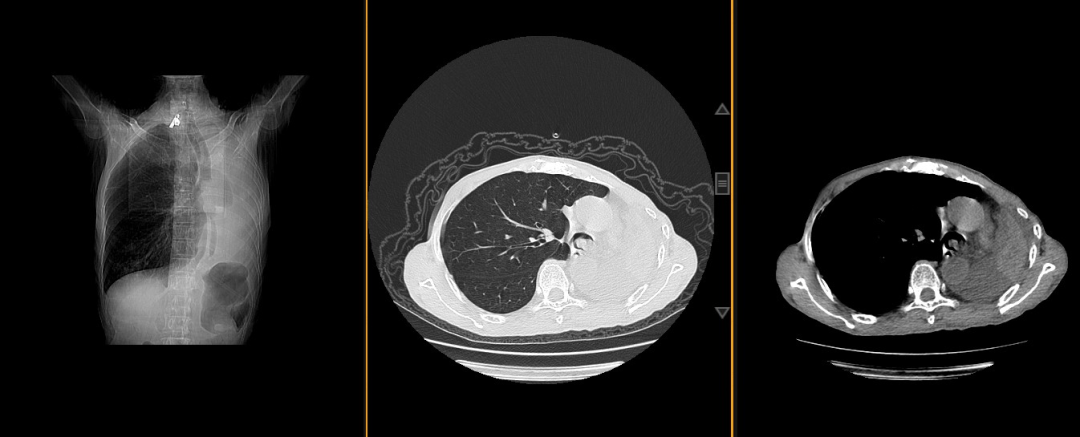

患者李大爷(化名)因咳嗽、胸闷半个月伴呼吸困难紧急入院,胸部CT检查提示气管及左主支气管内占位性病变,气管堵塞超90%,随时可能因窒息危及生命。呼吸诊疗中心团队快速完成病情评估,确诊为气管肿瘤引发的大气道重度狭窄,属呼吸介入诊疗急危重症,需立即通过介入技术解除梗阻。

全麻支气管镜下,呼吸诊疗中心八里湖病区吴健卫主任、徐非州主诊团队,采用高频电刀联合电圈套器环切术,对气管末端新生物分次套扎、精准切除。术中医护团队操作精准,顺利切除病灶并保障右侧主支气管通畅,术后创面无活动性出血,患者呼吸困难症状即刻显著改善,生命体征恢复平稳。切除的新生物已送病理检查,为后续诊疗方案制定提供核心依据。